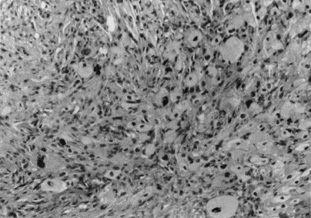

Histologically, melanoma can be classified based on the location in the skin (epidermal, dermal, subcutaneous), disposition and frequency (pagetoid, lentiginous, nested, single-cell infiltrating, nodular), morphologic features, and cell type (epithelioid, spindle, dendritic, nevuslike, small cell, balloon cell, clear cell, anaplastic giant cell, rhabdoid, signet ring). The most common type is intraepidermal pagetoid (also known as superficial spreading) with epithelioid or polygonal cell types; however, more than one cell type is often present. Principle histologic features distinguishing melanoma from dysplastic nevi and Spitz tumors include loss of rete ridges, uniform cytologic atypia, diminished or absent maturation of the dermal component of cells, patchy or bandlike mononuclear cell infiltrates that can be absent in thick melanomas, and increasing numbers of mitotic figures in the deeper dermis. Often, variable cytoplasm is present depending on cytologic type, and cells are highly pleomorphic, with high nuclear-to-cytoplasm ratios, hyperchromatism, prominent variable nucleoli, and thickened nuclear membranes.